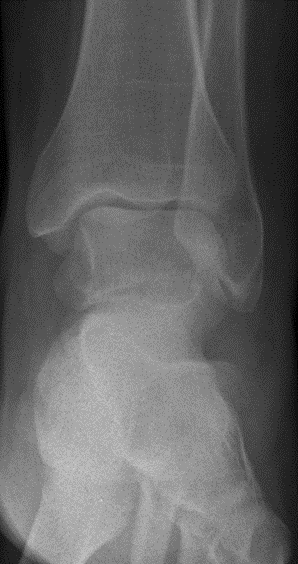

Bei Verschlechterung des Befundes erfolgte nach nunmehr 9 Wochen nach dem Unfall eine MRT Untersuchung, bei der sich ein unverschobener Bruch des Sprungbeinhalses ergab. (Abb. 3)

Abb. 3 MRT 9 Wochen nach dem Unfall